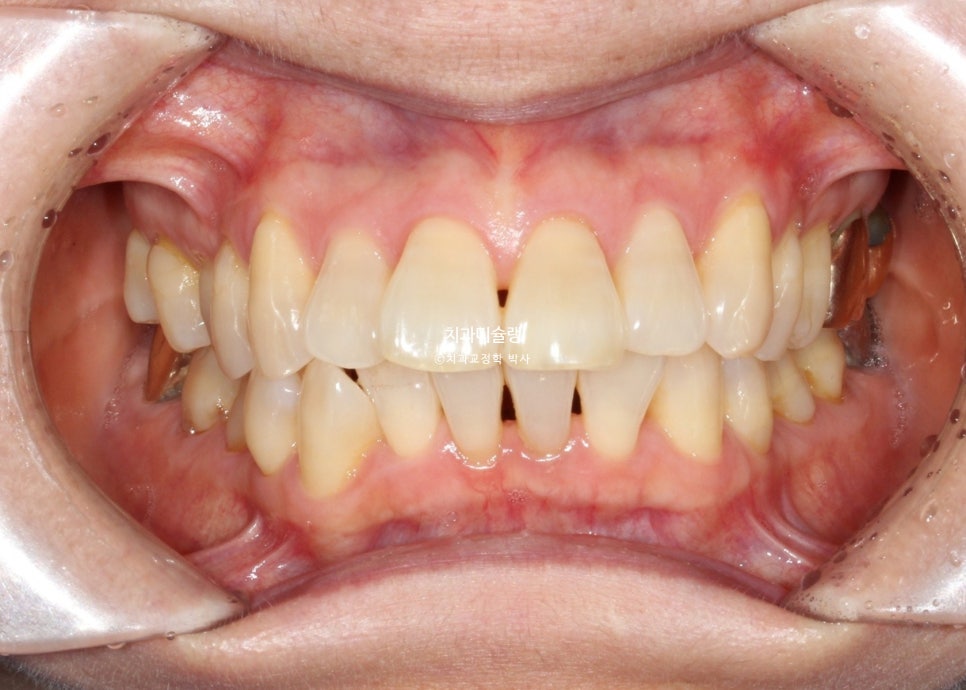

작년 여름, 앞니 돌출과 배열 개선을 위해 교정치료 상담을 오신 50대 환자분입니다.

앞니 사이 블랙트라이앵글이 눈에 띕니다.

아래 송곳니중 한쪽이 덧니라 거꾸로 물리는 반대교합도 있습니다.

앞니 돌출이 심해서 입이 편하게 다물리지 않습니다.

턱끝까지 힘을 주어야 다물리는 상태를 입술부전증 이라고 합니다.

턱끝에 힘이 들어가니 턱끝 모양이 늘 울퉁불퉁한 호두턱 자갈턱 상태입니다.